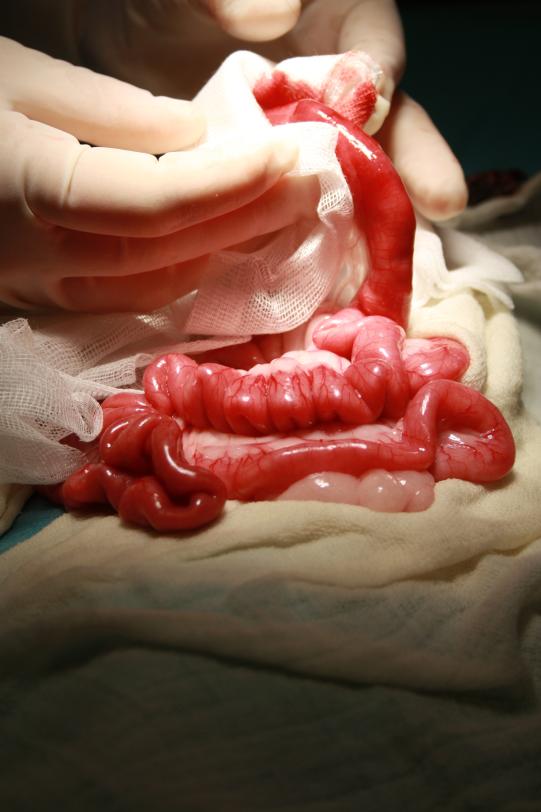

Die Katze wird über eine intravenöse Infusion stabilisiert, mit Schmerzmitteln und Antibiotika behandelt und schnellstmöglich in den OP verbracht. Hier ist erkennbar, dass ein schnurähnlicher, langer Fremdkörper im Dünndarm steckt und diesen schon so weit geschädigt hat, dass nach der Entfernung des Fremdkörpers ein ca. 20 cm langes Darmstück entfernt werden muss. Vorsichtig werden die Darmenden zusammengenäht und die Bauchwunde verschlossen. Der Kater bleibt noch drei weitere Tage hospitalisiert und wird danach nach Hause entlassen. Leider entwickelt sich nach der Operation auch noch eine Entzündung des Unterhautfettes, was eine erneute Hospitalisation notwendig macht und damit weitere Kosten verursacht. Schlussendlich kann der Kater aber als geheilt entlassen werden. Der Besitzer wird angehalten, sämtliche problematischen Spielzeuge zu entfernen, damit sich das Unglück nicht wiederholt. Bei der Entlassung der Katze ist der Besitzer dann doch in der Lage, eine Anzahlung